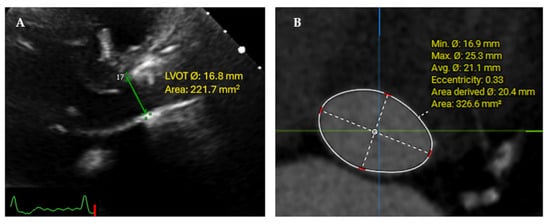

2.2. Echocardiography

| MDCT-derived LVOT measurements | |

|      Minimum diameter, mm Maximum diameter, mm LVOT area, mm2  | 19.03 (2.55) 26.92 (2.43) 405.22 (81.32)  |

| LVOT diameter, mm | 21.03 (1.9)  | Minimum diameter 19.03 (2.55) | [1.7, 2.31] |

| LVOT area, mm2 | 350.4 (62.04) | 405.22 (81.32) | [−55.15, −36.09] |